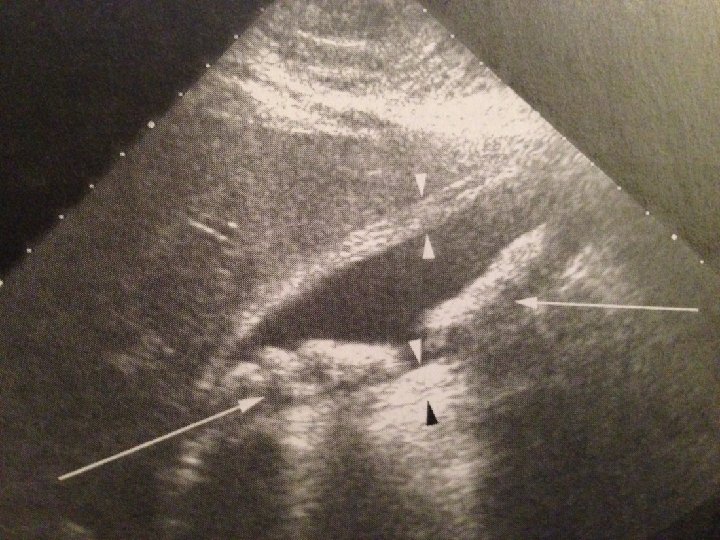

Görüntüleme • Düz film - Geniş safra kesesi gölgesi Safra kesesi taşı düz filmde %15 görülebilir. • US tarama – taş, çamur, duvarda kalınlaşma • Ultrasonik Murphy İşareti • Radyonüklit ekskresyon tarama ( HİDA )